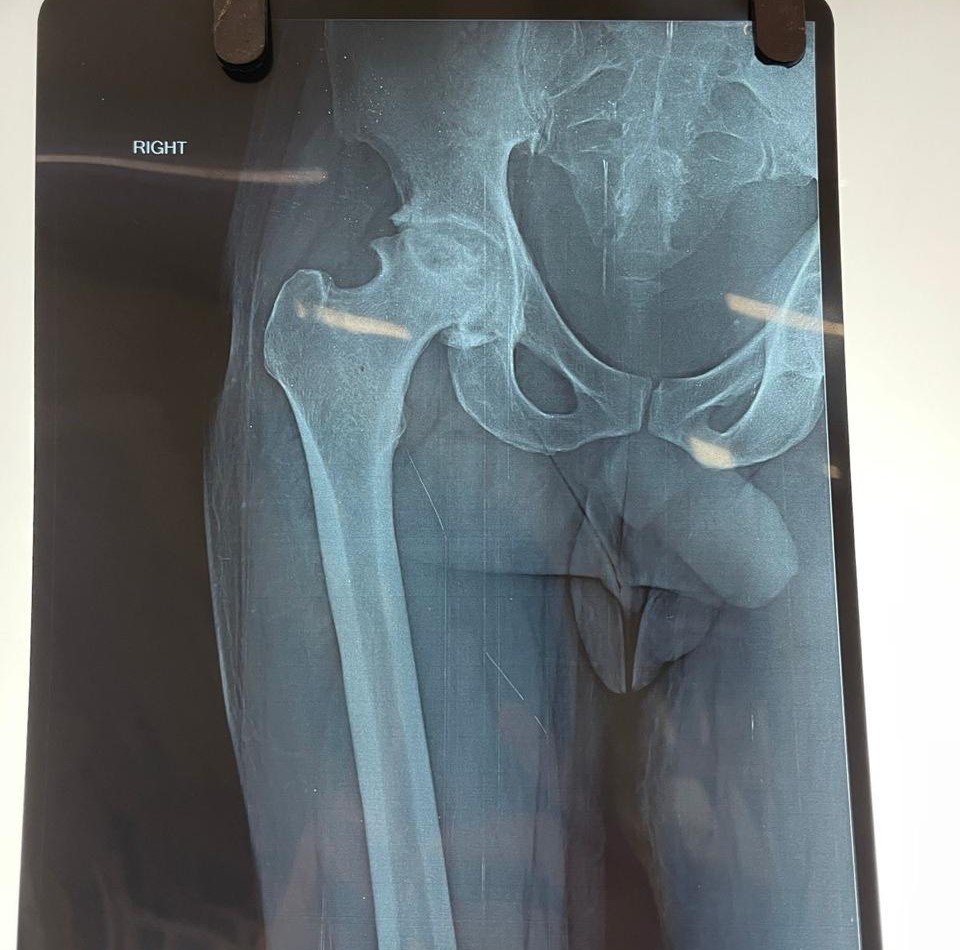

Total Hip Replacement is an advanced orthopedic surgical procedure performed to replace a damaged or worn-out hip joint with an artificial implant. The hip joint is one of the largest joints in the body and plays a crucial role in supporting body weight and enabling movements such as walking, sitting, and bending. When the hip joint becomes severely damaged due to arthritis, injury, or other degenerative conditions, it can cause chronic pain, stiffness, and difficulty in movement, significantly affecting a person’s quality of life.

Total Hip Replacement (THR) involves replacing the damaged parts of the hip joint with artificial components called prostheses. The procedure typically includes replacing the damaged ball of the thigh bone (femoral head) and the socket of the hip joint with specially designed implants made of metal, ceramic, or medical-grade plastic. These implants help recreate the smooth movement of a healthy hip joint and significantly reduce pain.

Before recommending surgery, Dr. Emad Ansari conducts a detailed clinical examination along with diagnostic tests such as X-rays, CT scans, or MRI scans to assess the condition of the hip joint. If non-surgical treatments like medications, physiotherapy, and lifestyle changes fail to provide relief, hip replacement surgery may be suggested as an effective long-term solution.